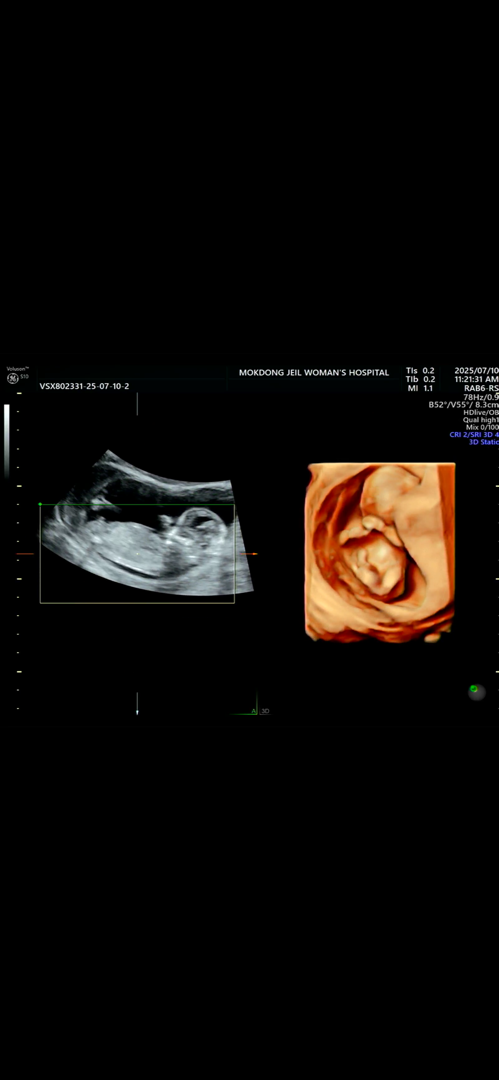

13주 2일차 각도법...! 궁금해요ㅠㅠ잘보시는분!!

안녕하세요~~~ 입초로 보니까 더 귀여워요..ㅠㅠ💖 초기니까 볼까말까 고민했는데 보길 잘했다!!! 였습니다 ㅎㅎㅎㅎ 나름 선명한 촘파사진인데! 각도법 고수님들 한번만 성별 봐주세요!!!😍